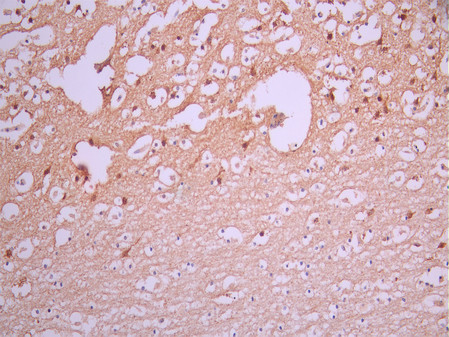

IHC image of CSB-RA236968A0HU diluted at 1:100 and staining in paraffin-embedded human brain tissue performed on a Leica BondTM system. After dewaxing and hydration, antigen retrieval was mediated by high pressure in a citrate buffer (pH 6.0). Section was blocked with 10% normal goat serum 30min at RT. Then primary antibody (1% BSA) was incubated at 4°C overnight. The primary is detected by a Goat anti-rabbit polymer IgG labeled by HRP and visualized using 0.05% DAB.